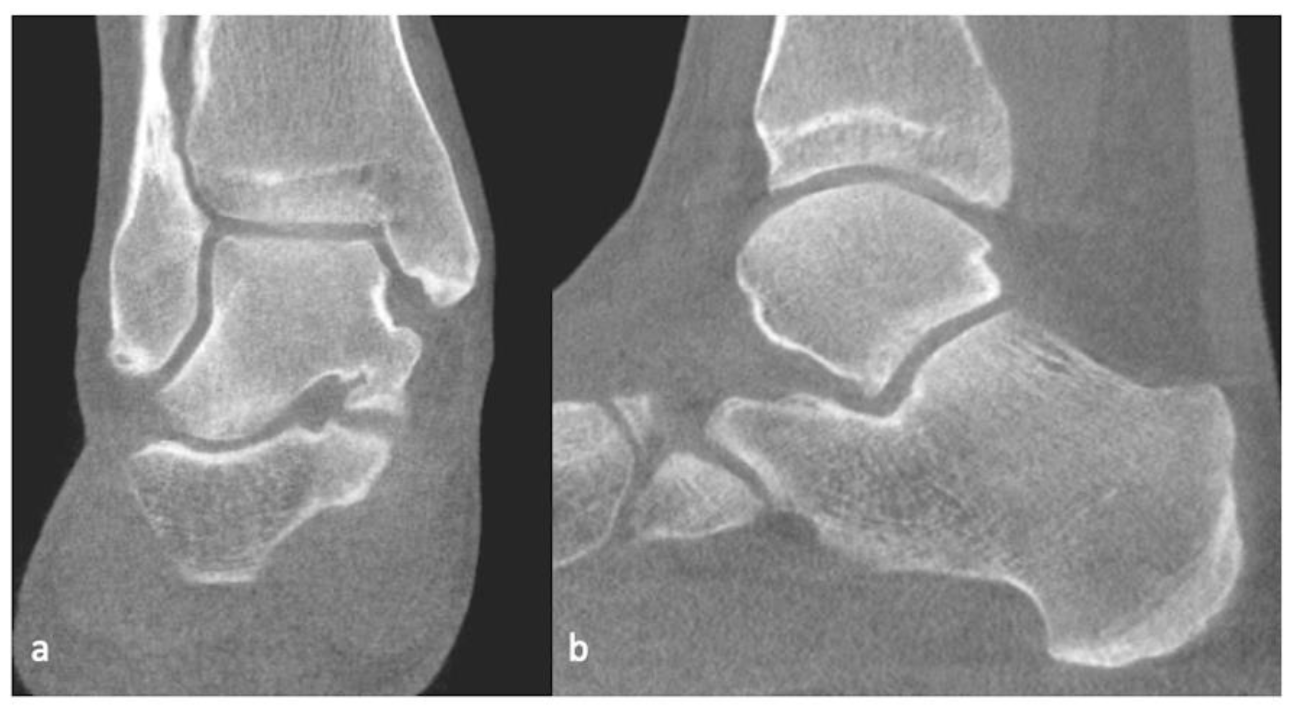

3.3. CT/CT Arthrogram

| Berndt and Harty (X-ray) | Loomer et al. [57] Modification (CT) | Hepple et al. [58] (MRI) |